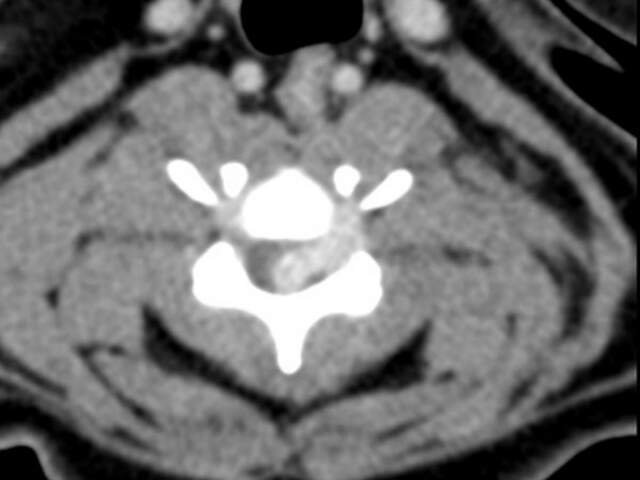

Je nach Art der Erkrankung sind weitergehende Untersuchungen notwendig. So ist bei einem akuten Bandscheibenvorfall eine Computertomografie (CT) mit Kontrastmittel bzw eine Myelo- CT des Rückenmarkkanals angezeigt. Bei Verdacht auf entzündliche oder tumoröse Erkrankungen des zentralen Nervensystems sollte eine Untersuchung der Gehirn-und Rückenmarksflüssigkeit (Liquoruntersuchung) erfolgen. In einigen Fällen kann man eine genaue Diagnose nur durch eine Magnetresonanztomografie (MRT) oder durch die Elektrodiagnostik stellen. Hier ist die gute Zusammenarbeit mit Universitäts- bzw. Spezialkliniken erforderlich.